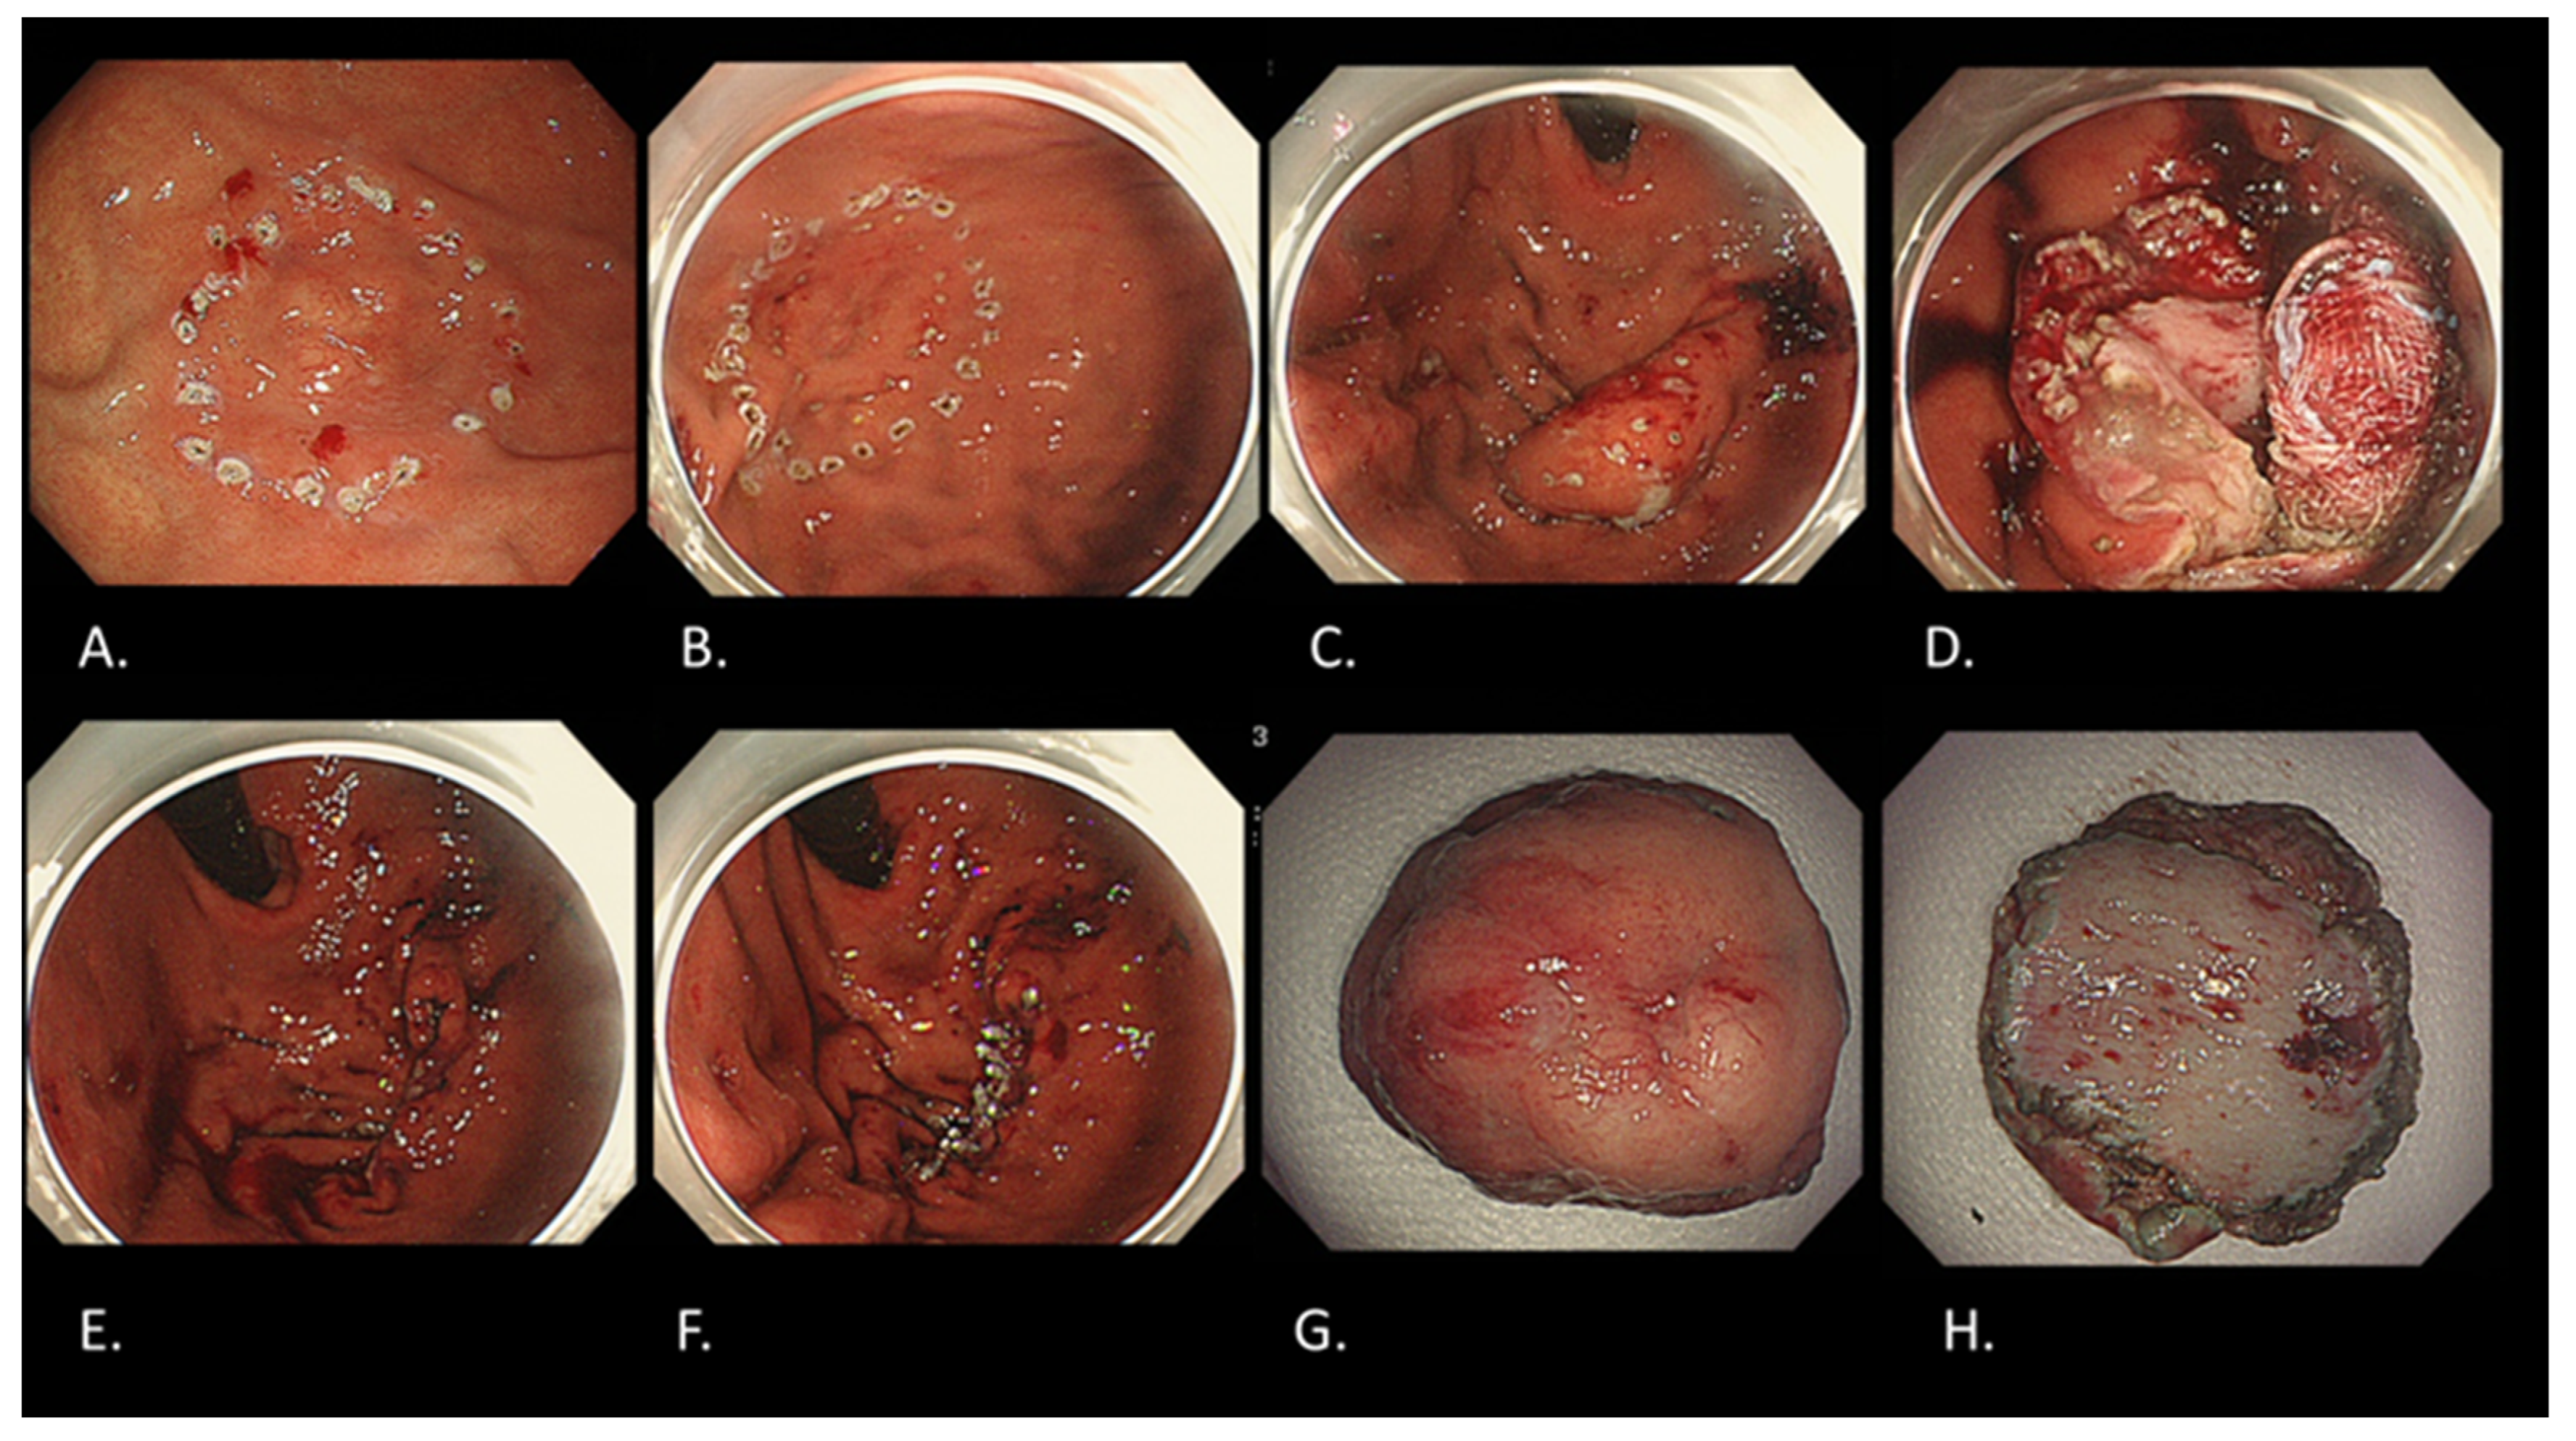

5. Types of Endoscopic Resection for Early Gastric Cancer